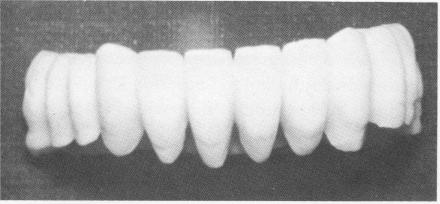

Fig. 13-47. The acrylic full arch splint. It can be worn either with temporary cement or with no cement at all, allowing it to be taken off and placed back on at will.

5 Mandibular acrylic full arch splint